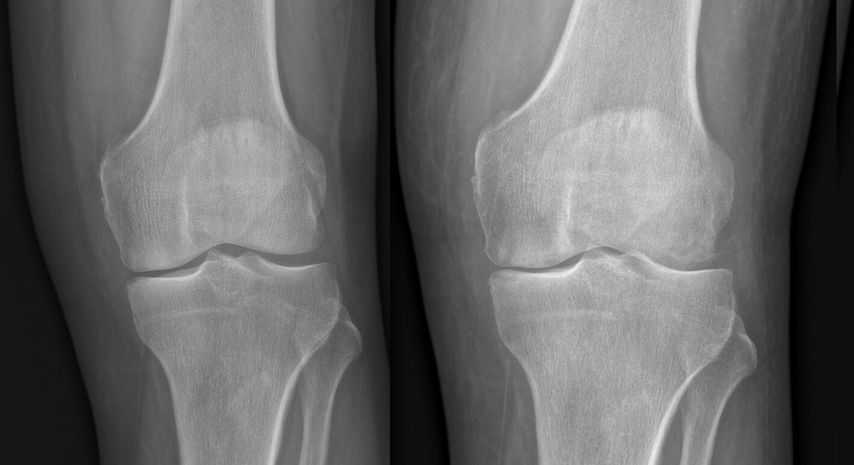

Abb. 1: Zunehmende Gelenksdestruktion mit subchondralen Osteolysen innerhalb weniger Wochen im Vergleich mit dem Vorbefund

Die chirurgische Therapie ist so schnell wie möglich durchzuführen, wobei sie bei milderen Verläufen ohne systemische Affektion nicht notfallsmäßig, etwa in der Nacht, erfolgen muss.13 Zur initialen operativen Sanierung stehen die Arthroskopie sowie die offene Arthrotomie als therapeutische Optionen zur Verfügung. Diese sollten eine ausgiebige Spülung und gegebenenfalls, je nach Befund, ein Débridement mit einer Synovektomie beinhalten. Bei unbekanntem Infektstadium ist die Arthroskopie auf jeden Fall als initiale Therapie zu bevorzugen. Bei fortgeschrittenem Infektstadium sind wiederholte Arthroskopien oder der Wechsel auf eine offene Arthrotomie, um ein ausreichendes Débridement zu erreichen, notwendig.4,5,9,27